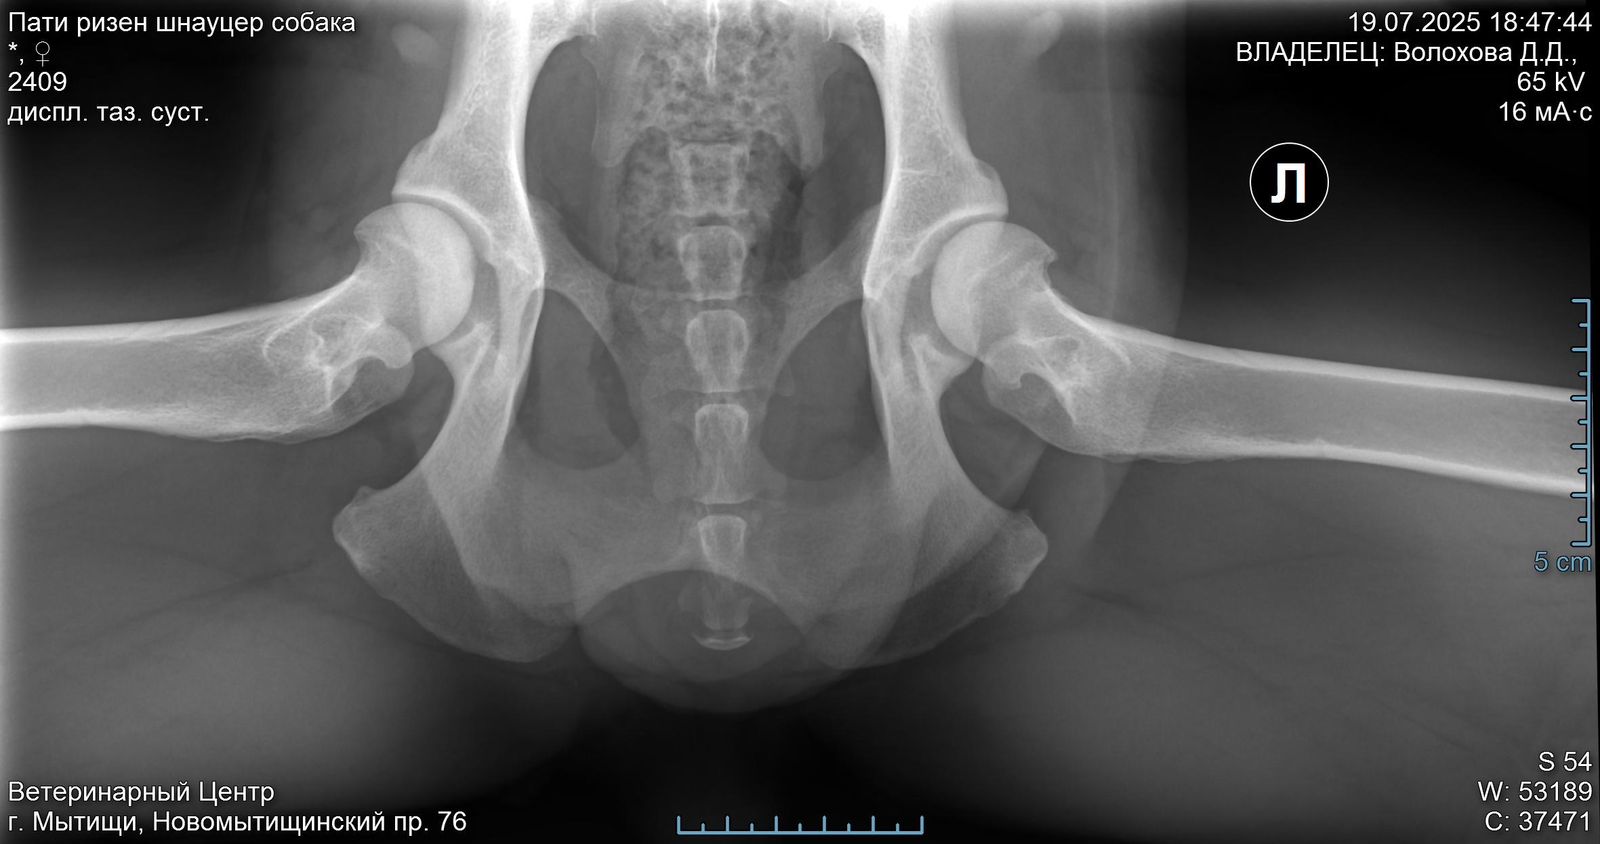

Задние ноги не идеал, но портить жизнь не должны.